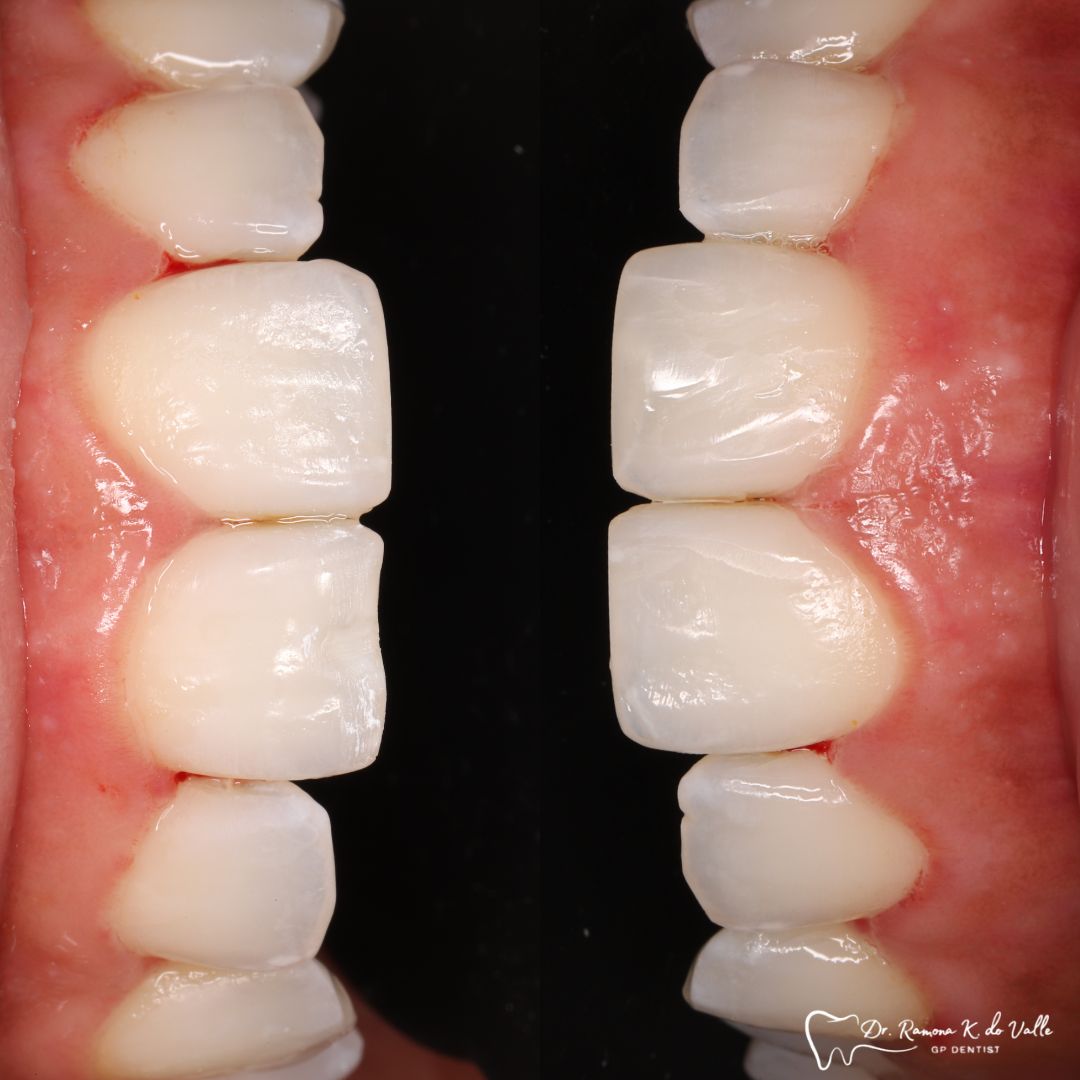

3. Layering the Composite Resin

The tooth-coloured resin is applied in thin layers and shaped carefully to match natural anatomy. For front-tooth work, we may combine several shades for a lifelike result.

• fixing chipped or worn edges

• closing minor gaps

• correcting tooth shape asymmetry